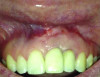

Fig 15 and Fig 16. Case 2: Clinical view (Fig 15) and radiograph (Fig 16) at 12-month follow-up confirming resolution of the peri-implant defect.

Figure 15

Fig 16. Case 2: Clinical view (Fig 15) and radiograph (Fig 16) at 12-month follow-up confirming resolution of the peri-implant defect.

The 12-month and 7-year follow-ups for case 2 showed similar improvements with normal soft-tissue healing and bone fill and normal pocket depths at 12 months (Figure 15 and Figure 16) and 7 years post-treatment (Figure 17 and Figure 18) (Table 1).